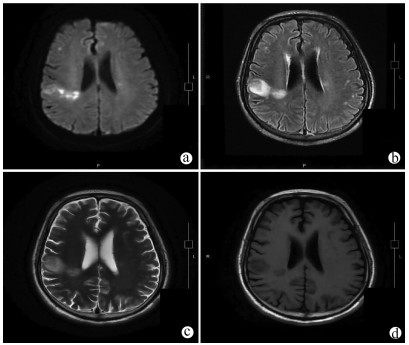

A case of acute cerebral infarction with splenic rupture secondary to splenic infarction

Qin YU, Chen CHEN, Qian XIA, Jin CHEN

2021, 37(10): 2417-2419. DOI: 10.3969/j.issn.1001-5256.2021.10.033

Abstract(947) HTML (288) PDF (2433KB)(44)